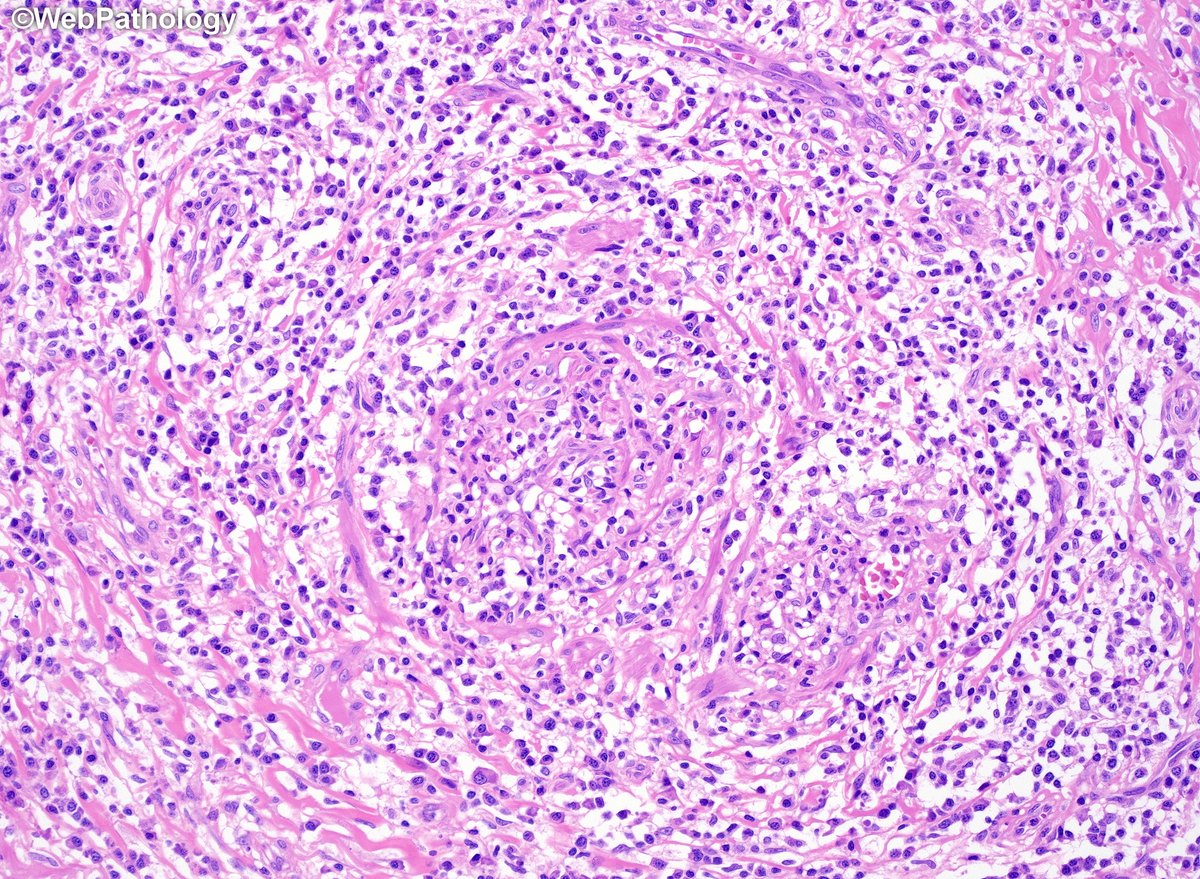

Adult male with a large ulcerated and indurated lesion on foreskin. What would you do next? Additional images and diagnosis will be posted later. #gupath

WebPathology's tweet image. Adult male with a large ulcerated and indurated lesion on foreskin. What would you do next? Additional images and diagnosis will be posted later. #gupath